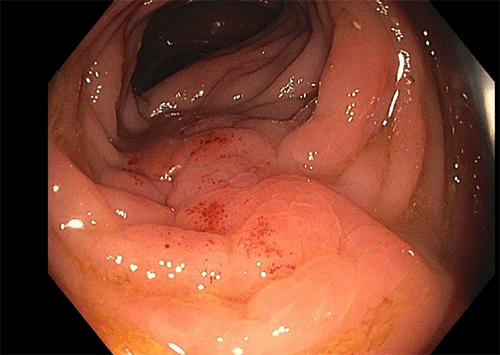

A 72-year-old Hispanic male with chronic kidney disease and type II diabetes was seen at the colon and rectal surgery clinic at John H. Stroger Hospital of Cook County for a suspicious colonic mass near the hepatic flexure. The patient initially complained of left flank pain and weight loss. A computerized tomography (CT) scan of the chest, abdomen, and pelvis showed a 3.5 × 3.5 cm lesion at the hepatic flexure associated with fat stranding, likely representative of direct local infiltration, multiple mesenteric lymph nodes and no sign of distant metastasis (Figure 1). Carcinoembryonic antigen level (CEA) was 1.34 ng/mL. He underwent a diagnostic colonoscopy with a biopsy of the lesion, revealing findings consistent with an inflammatory process (Figure 2).

Figure 1. First Abdominal CT Scan Showing Hepatic Flexure Lesion. Published with Permission

Figure 2. First Colonoscopy Showing Intraluminal Mass. Published with Permission